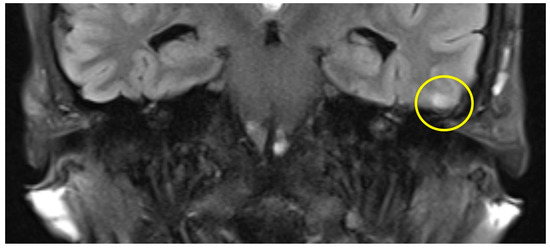

| slight (1) | parts of the inferior temporal gyrus, less than half of the thickness (cranial-caudal) |

| moderate (2) | further parts of the inferior temporal gyrus |

| Patient #1 | T2 | f | 58 | left | 12 months | 175 min | slight |

| Patient #2 | T2 | f | 62 | right | 16 months | 159 min | slight |

| Patient #3 | T2 | f | 57 | left | 11 months | 131 min | slight |

| Patient #4 | T1 | f | 49 | left | 12 months | 159 min | slight |